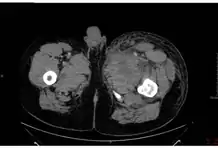

In December 2009, an outbreak of anthrax occurred among injecting heroin users in the Glasgow and Stirling areas of Scotland, resulting in 14 deaths.[23] This became the first documented non-occupational human anthrax outbreak in the UK since 1960.[23] The source of the anthrax is believed to have been dilution of the heroin with bone meal in Afghanistan.[24] Injected anthrax may have symptoms similar to cutaneous anthrax, with the exception of black areas,[25] and may also cause infection deep into the muscle and spread faster.[26] This can cause it to be harder to recognise and treat.